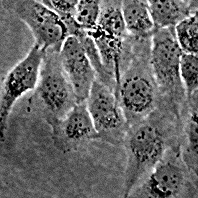

XPA (XP12RO)

Происхождение: человек, фибробласты больных пигментной ксеродермой, трансформированные SV 40.

Морфология: фибробластоподобная

Кариология: 2n = 46, пределы изменчивости по числу хромосом 55-75, модальное число 68-70, количество маркеров –19% клеток содержат дицентрик (рутинная окраска), 7% клеток содержат микрохромосому, количество полиплоидов 5.0%.